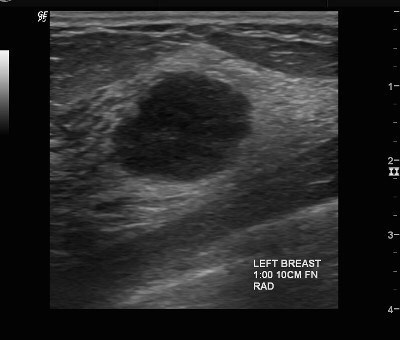

👉The sonographic image in this patient shows a fairly round, well-circumscribed, microlobulated lesion with posterior enhancement.

👉The most reliable sonographic feature of medullary carcinoma is enhanced through transmission.

👉This results from the highly cellular lesion with a paucity of desmoplastic fibrous tissue, in addition to areas of cystic necrosis and hemorrhage.

👉Medullary carcinomas are classically well-circumscribed, but most of them have some area of angularity.

👉High-grade, colloid (mucinous), and papillary carcinomas typically have a sonographic appearance similar to medullary carcinoma.